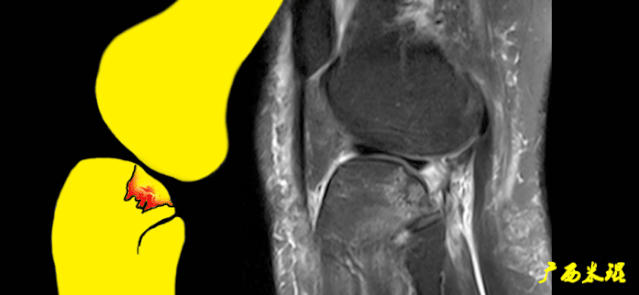

5)撕脱骨折:

-

一般为ACL胫骨附着部的撕脱。

韧带完整,信号多正常。